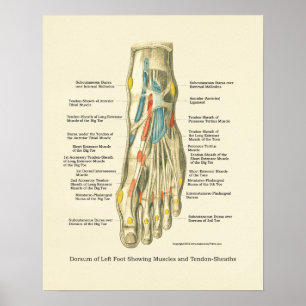

Poster d'anatomie du pied et de la cheville

Prix48.05 CHF

Poster Une antique des muscles des jambes et des pieds

Prix189.00 CHF

Poster d'anatomie interne Pied & Ankle

Prix32.95 CHF